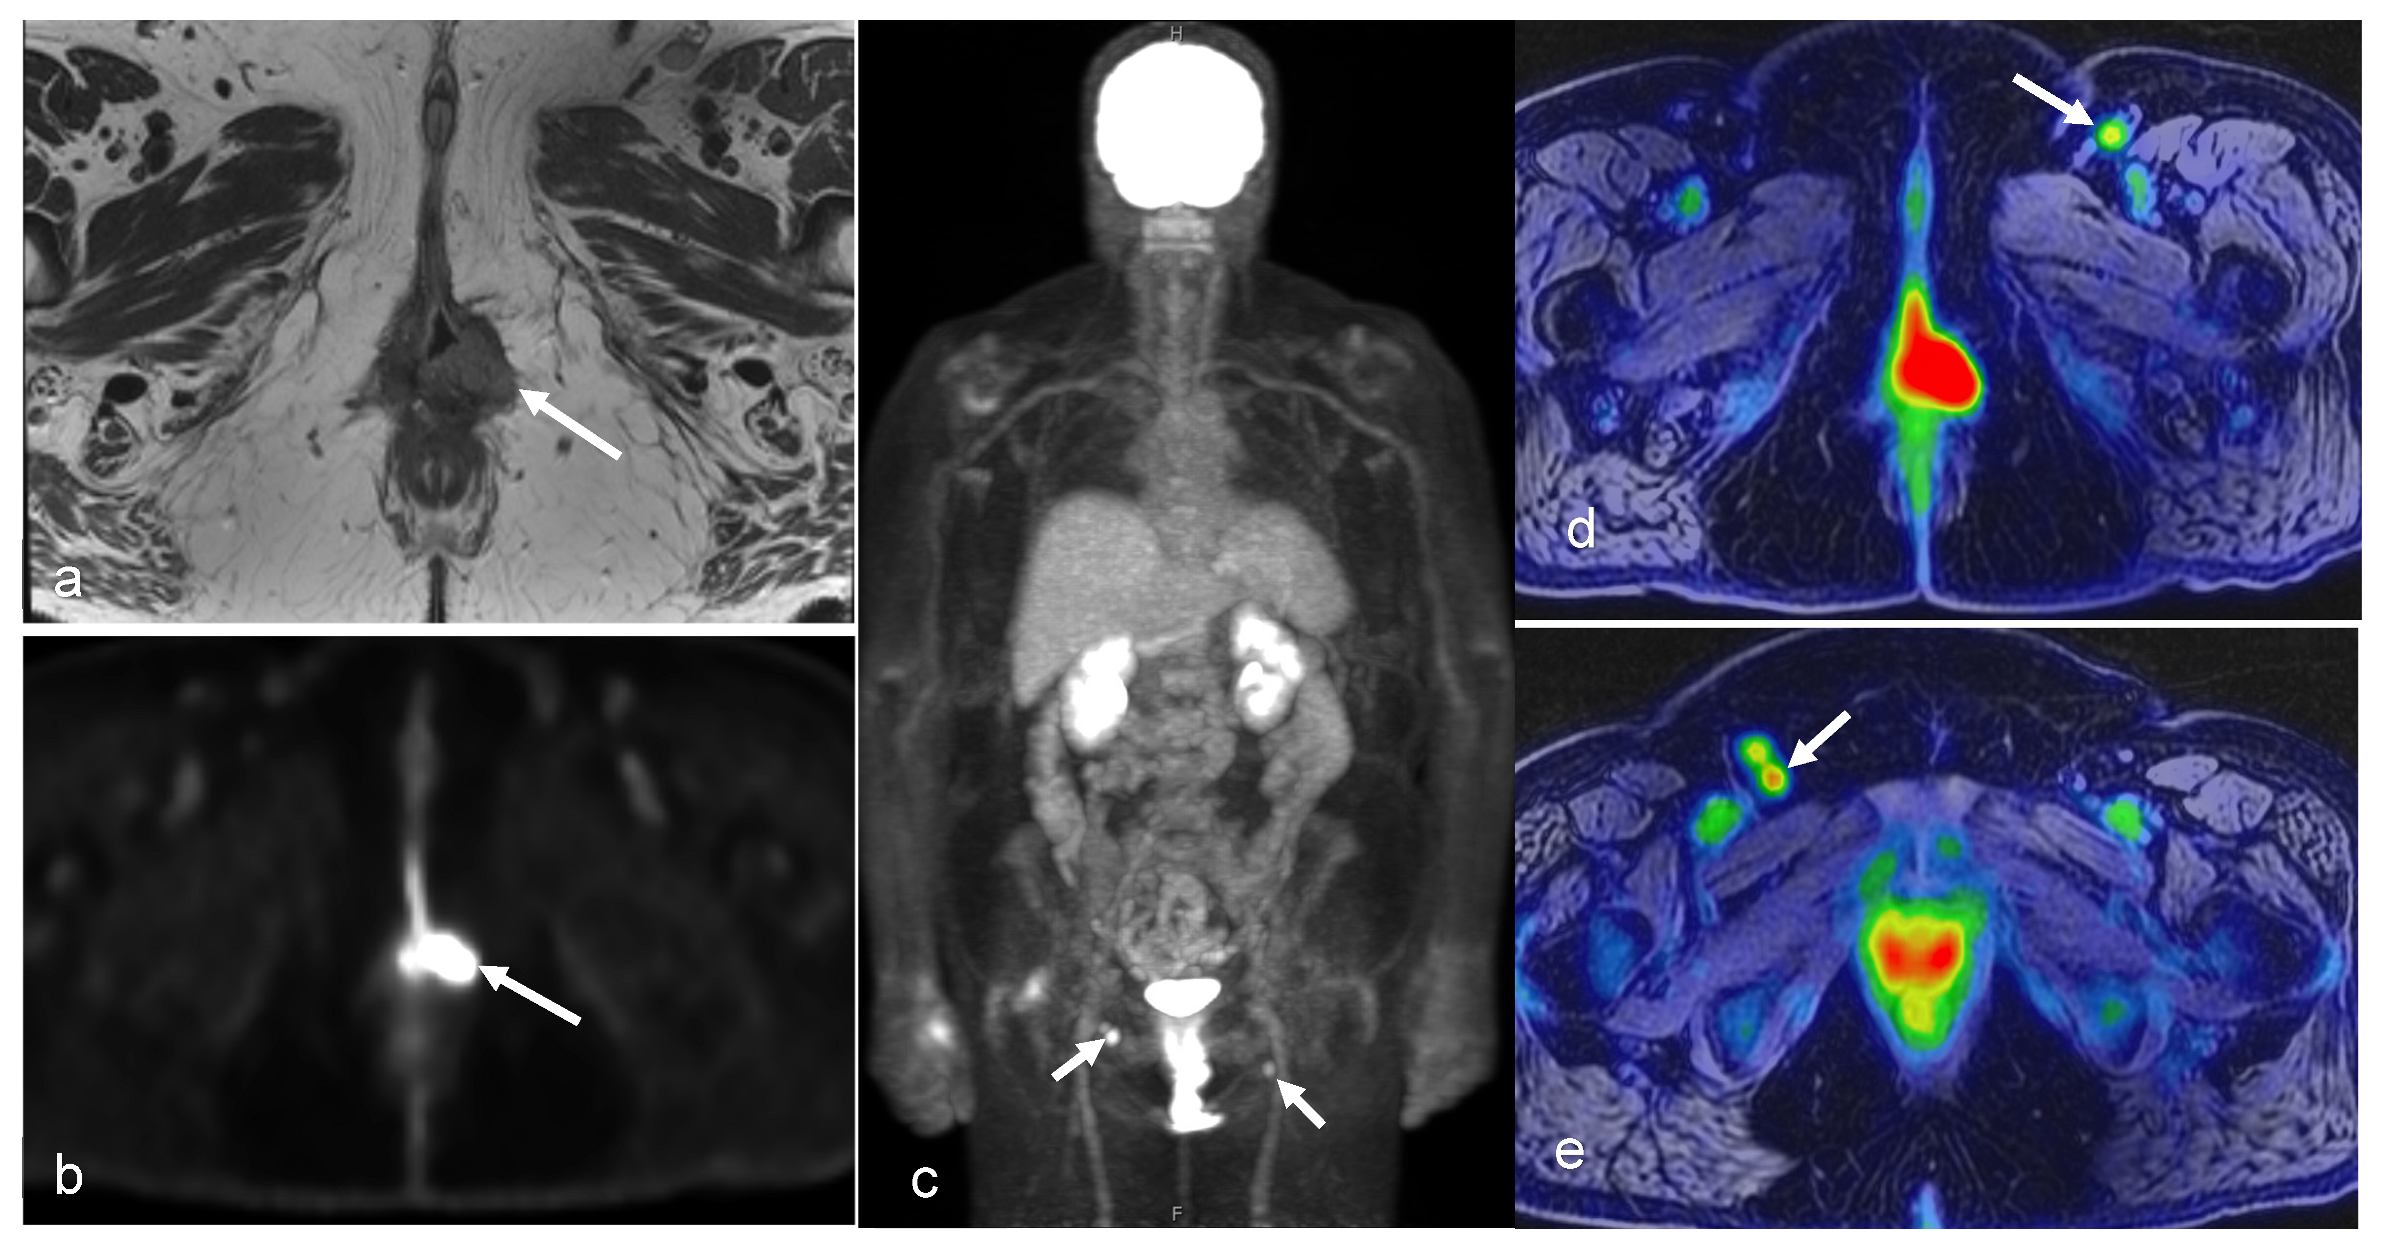

3.4. Vaginal and Vulvar Cancers